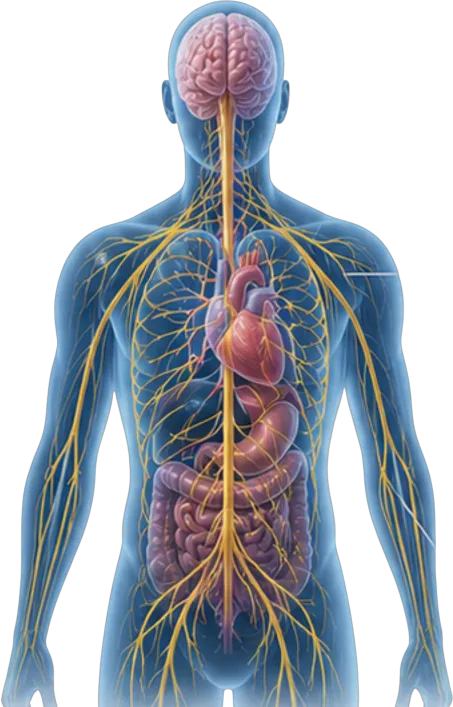

The Clinical Gap

Are we only treating the symptoms…

while overlooking the system behind them?

A significant subset of patients diagnosed with depression do not respond to standard therapies.

They are often labeled “treatment-resistant,” leading to medication escalation rather than deeper investigation.

Emerging evidence suggests something important:

In many of these patients, the issue may not originate in brain chemistry alone.

Instead, it may involve dysfunction in the autonomic nervous system—the system responsible for regulating the body’s most critical moment-to-moment functions, including heart rate, blood pressure, and cerebral blood flow.

The Missing System

The Autonomic Nervous System

The brain does not function in isolation.

It depends on stable physiological regulation to receive consistent oxygen and nutrient delivery.